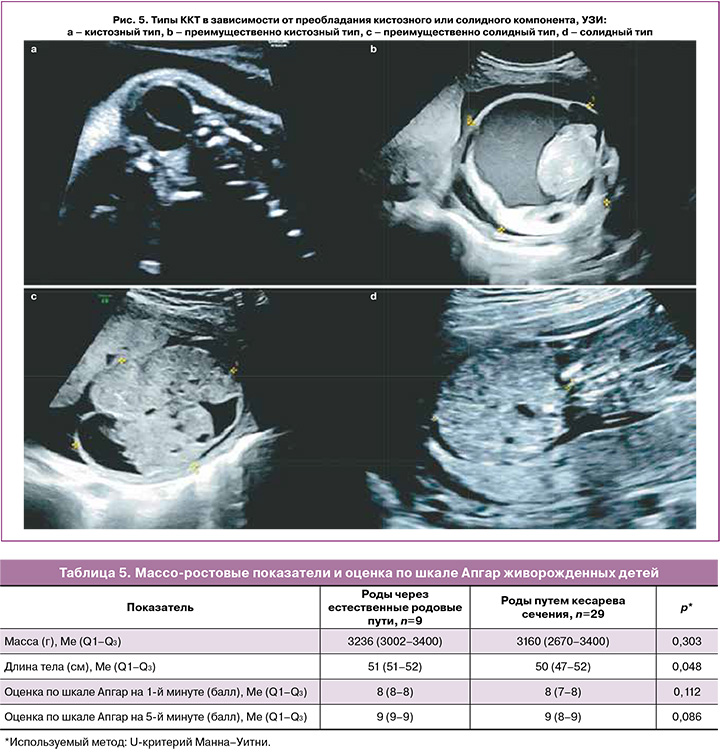

При проведении УЗИ определяли структуру ККТ и в зависимости от соотношения кистозного и солидного компонентов выделяли 4 варианта (рис. 1) [9]:

- кистозная ККТ – более 90% опухоли представлено кистами;

- преимущественно кистозная ККТ – 50–90% опухоли представлено кистами;

- преимущественно солидная ККТ – 50–90% опухоли представлено солидным компонентом;

- солидная ККТ – более 90% опухоли представлено солидным компонентом.

ККТ кистозного строения (рис. 5а) и преимущественно кистозного (рис. 5b) встречались почти с равной частотой – 15,3 и 18,6% случаев соответственно. Наиболее часто ККТ были представлены преимущественно солидным компонентом (рис. 5с) – 54,2%, в то время как ККТ с солидным строением (рис. 5d) встречались наиболее редко и составили 11,9% случаев. На рисунке 5 представлены примеры ККТ различных типов строения.